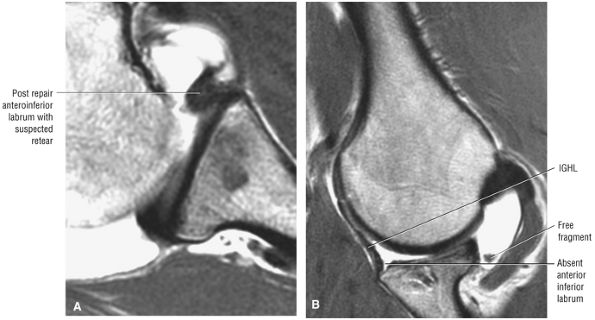

|

FIGURE 8.154 ● An isolated infraspinatus tendon tear shown on (A) a posterior superior color illustration, (B) a posterior coronal FS PD FSE image, and (C) a sagittal FS PD FSE image.

![]() |

FIGURE 8.155 ● Increased cross-sectional diameter “sign” of a retracted infraspinatus tendon in an isolated tendon tear of the rotator cuff is seen on (A) sagittal FS PD FSE and (B) coronal FS PD FSE images. Increased tendon diameter is useful as a secondary sign of supraspinatus or infraspinatus tendon retraction.